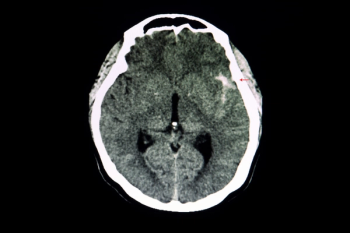

For patients who had neuroradiological trauma CT scans, researchers noted no significant visual differences between deep learning denoising at 25% mAs and iterative reconstruction at 100% mAs.